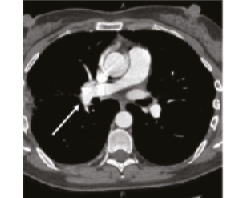

В 1993 г. на основании характерных признаков электрокардиограммы (ЭКГ) при профилактическом обследовании диагностирован феномен Вольфа–Паркинсона–Уайта. Клинических проявлений, снижающих качество жизни, пациентка не отмечала. К врачам далее не обращалась. В связи с появлением в 2015 г. одышки, перебоев в работе сердца, сердцебиения наблюдалась у участкового терапевта с диагнозом: ишемическая болезнь сердца, гипертоническая болезнь. Эхокардиография (ЭхоКГ), нагрузочные тесты не проводились. На фоне приема лозартана 25 мг/сут достигнуты целевые значения АД. В январе 2017 г. в связи с зарегистрированным на ЭКГ пароксизмом тахикардии с узкими комплексами QRS пациентка в порядке скорой помощи поступила с диагнозом «пароксизмальная суправентрикулярная тахикардия» в ЦРБ, где ритм был медикаментозно восстановлен. Далее в краевой больнице проведено внутрисердечное электрофизиологическое исследование и по его результатам – радиочастотная аблация дополнительных проводящих путей. Послеоперационный период протекал без осложнений. Однако в июне 2017 г. вновь появилась одышка при выполнении привычного объема физической нагрузки. По данным ЭКГ и рентгенограммы органов грудной клетки патологии не выявлено. Вскоре появилось кровохарканье (в течение 3 дней), и пациентка была направлена к фтизиатру, которым исключен туберкулез легких. 27.07.2017 на фоне значительного усиления одышки, выраженной тахикардии она потеряла сознание и в порядке скорой помощи доставлена в дежурный стационар, где травматологом и неврологом исключены сотрясение головного мозга и закрытая черепно-мозговая травма. Пациентка отпущена домой. В связи с сохраняющейся одышкой при подъеме на один лестничный пролет в августе 2017 г. по собственной инициативе она обратилась к кардиологу. При проведении ЭхоКГ выявлены увеличение правых камер сердца и признаки их объемной перегрузки. С предварительным диагнозом ТЭЛА пациентка направлена в дежурный стационар, где в экстренном порядке проведена спиральная компьютерная томография (СКТ) с контрастированием легочной артерии. Выявлены признаки легочной тромбоэмболии крупных и средних ветвей легочной артерии (ЛА) с обеих сторон (рис. 1–4). При целенаправленном сборе анамнеза выяснилось, что в течение 3 лет (с 2014 г.) пациентка принимает Линдинет 20 мг – монофазный пероральный контрацептив (этинилэстрадиол + гестоден), назначенный гинекологом с целью контрацепции. По данным ультразвукового исследования вен нижних конечностей выявлен тромбоз суральных вен справа. Линдинет отменен. На фоне лечения антикоагулянтами (гепарин, эноксапарин) состояние женщины несколько улучшилось. Она переведена на варфарин, который далее заменен на апиксабан в дозе 10 мг 2 раза в день.

Рис. 1: а – тромбы в верхнедолевой ветви левой ЛА; б – верхнедолевая ветвь левой ЛА проходима. | |

Рис. 2: а – тромбы в правой ЛА и нижнедолевой ветви левой ЛА; б – правая ЛА и нижнедолевая ветвь левой ЛА проходимы. | |

Рис. 3: а – тромбы в нижнедолевой ветви левой ЛА и нижнедолевой ветви правой ЛА; б – сохраняется тромбоз нижнедолевой ветви правой ЛА. | |

Рис. 4: а – тромбы в левой ЛА и ее ветвях; б – тромбоза левой ЛА (нисходящей ветви) не выявлено, сохраняется тромбоз нижнедолевой ветви левой ЛА. | |